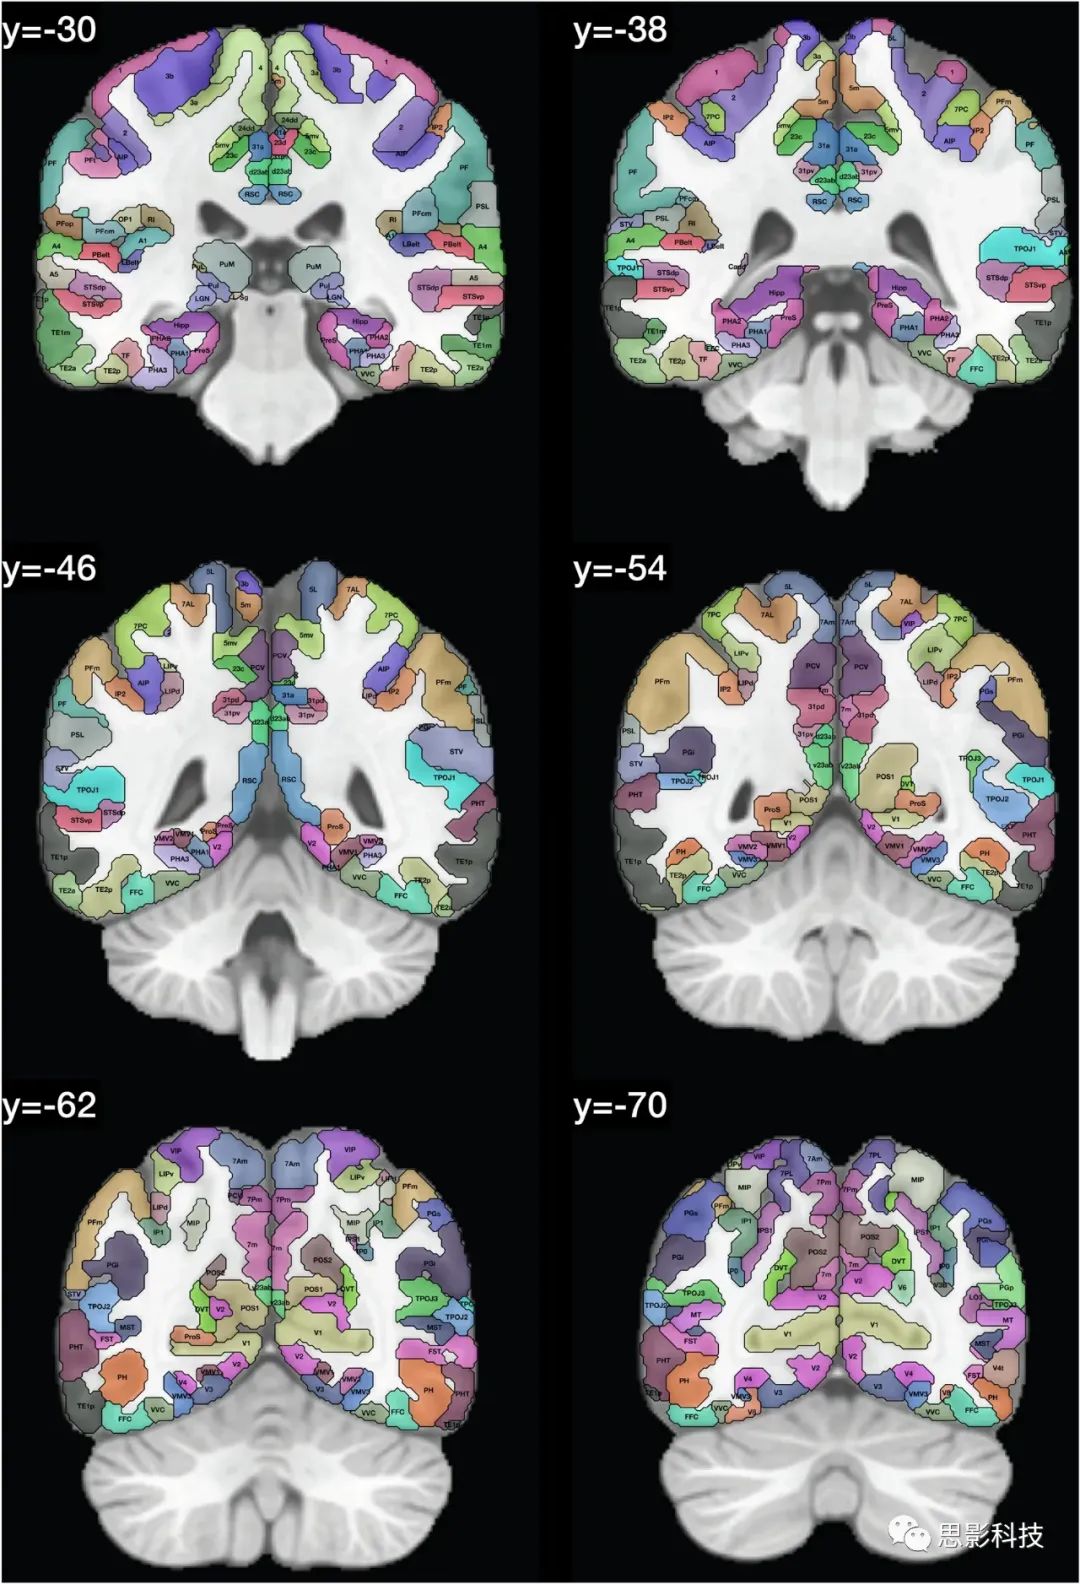

在人类连接组计划(HCP)图谱中区域的定义显示在Glasser et al.(2016a, b)的Glasser_2016_Table.xlsx中。这些区域的列表提供在表1中,并且在图1中,我们展示了带有在HCPex图谱中定义的区域标签的冠状切片。图1中的皮层区域是按照人类连接组计划(HCP)图谱(Glasser et al. 2016a)中的定义来的。

图1:展示了HCPex图谱中定义的区域和新增的皮层下区域的示例冠状切片。这些切片中使用的缩写与表1中的相同。这些冠状切片的y轴坐标是根据MNI(蒙特利尔神经学研究所)坐标系统来确定的。

图1提供了扩展HCP图谱的标记版本,以帮助读者识别这些人脑冠状切片中的脑区域。值得注意的是,一些小的脑结构在这些冠状切片中可能显得非常小,因为它们是被8毫米分隔开的(例如隔核就位于MNI坐标y:3–10之间)。表1和表2提供了图谱中脑区域的列表。在这个重新排序的列表中,标签列表提供在HCPex_LabelID.mat中。

本文描述的HCPex图谱扩展了HCP-MMP1图谱(Glasser et al. 2016a),通过增加66个皮下区域,以体积(volume)形式提供以适用于多种类型的神经影像软件,包括SPM,提供带标签的大脑冠状切片以清晰可视化HCPex图谱中定义的皮层和皮下区域(图1),并提供图谱中皮层区域的可选重排序(表1)。我们已经发现,有了这些扩展,HCPex图谱非常有帮助(Huang et al. 2021; Ma et al. 2021; Rolls et al. 2021)。

总之,这里描述的HCPex图谱通过增加66个皮层下区域、以体积(Volume)形式提供以适用于多种类型的神经影像软件(包括SPM)、提供带标签的大脑冠状切片以清晰可视化HCPex图谱中定义的皮层和皮层下区域(图1)以及提供图谱中皮层区域的可选重排序(表1),从而扩展了HCP-MMP1图谱(Glasser et al. 2016a)。